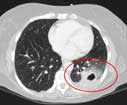

- CT of the lungs (www.radiologyresource.org/en/info.cfm?pg=chestct): A CT scan of the chest may be done to see finer details within the lungs and detect pneumonia that may be more difficult to see on a plain x-ray. A CT scan also shows the airway (trachea and bronchi) in great detail and can help determine if pneumonia may be related to a problem within the airway. A CT scan can also show complications of pneumonia, abscesses or pleural effusions and enlarged lymph nodes.

Images: Images are shown for illustrative purposes. Do not attempt to draw conclusions or make diagnoses by comparing these images to other medical images, particularly your own. Only qualified physicians should interpret images; the radiologist is the physician expert trained in medical imaging.